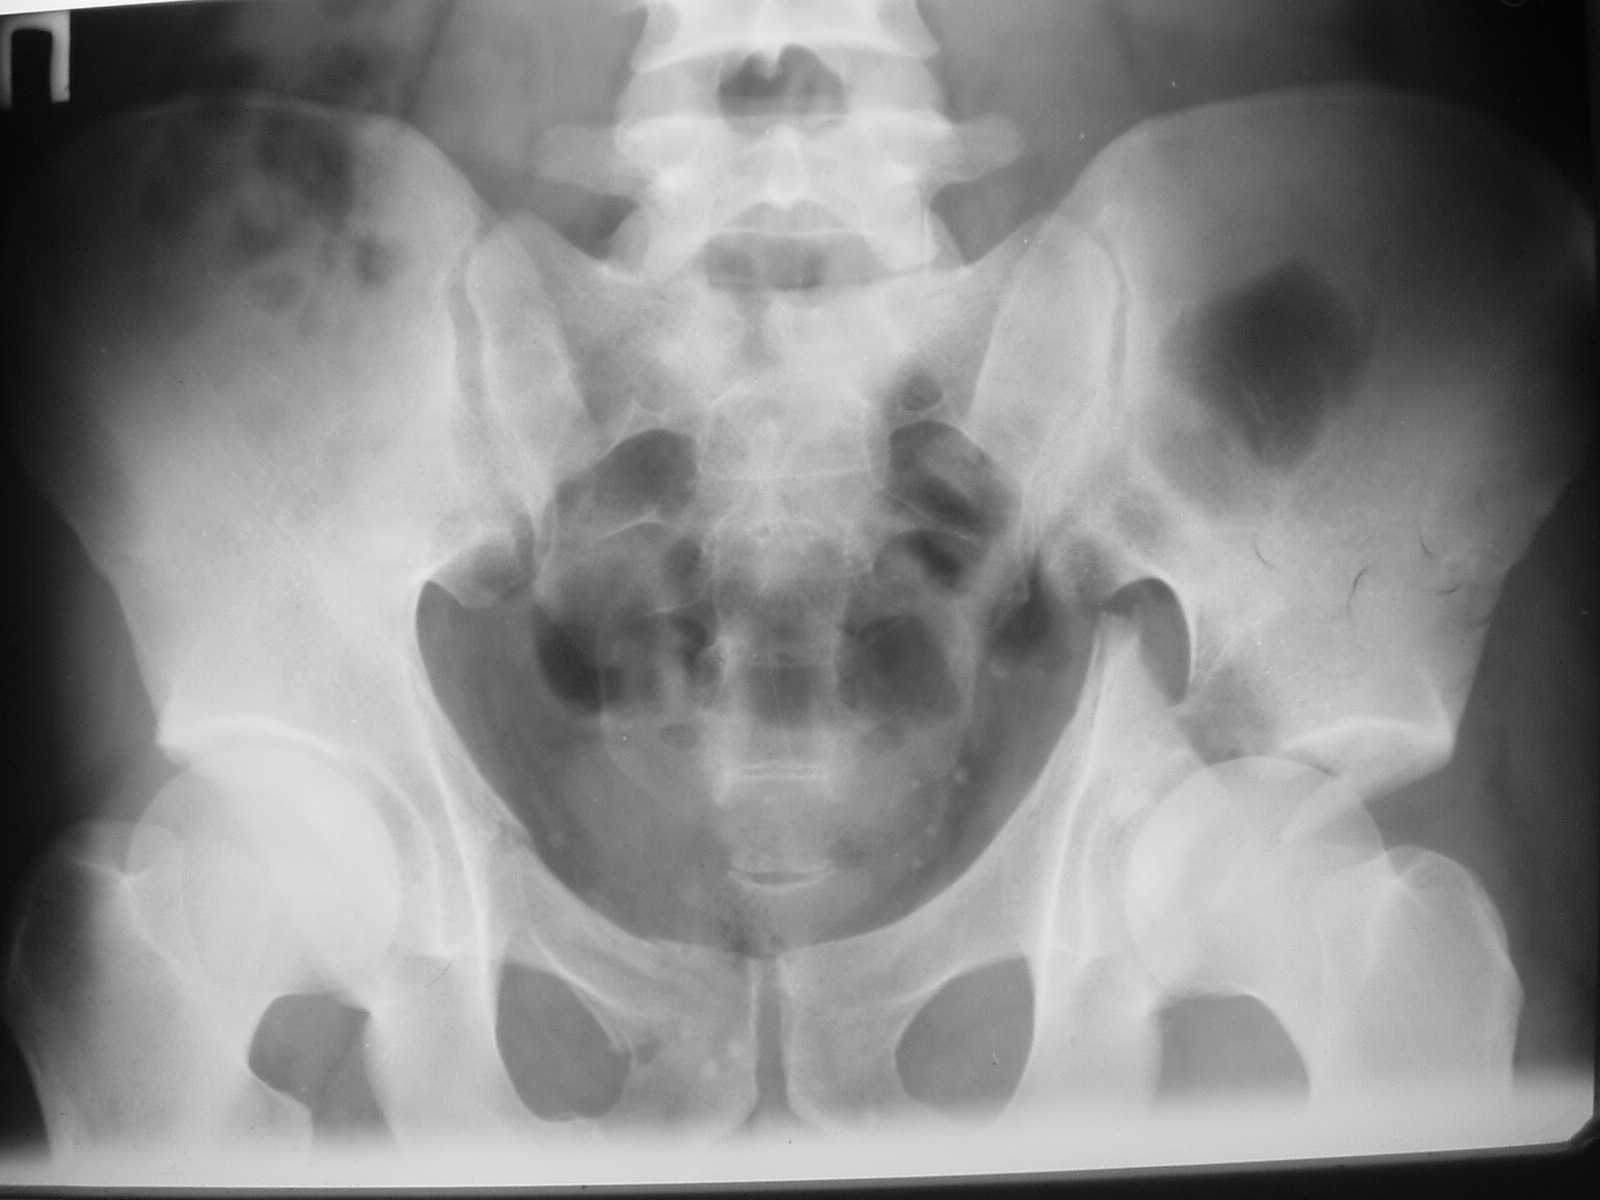

Dear dr Yordan ! I would do internal fixation as soon as possible. I sent to you one of my case with using of anterior iliofemoral approach - 5-th day after the accident. Best regards. Anatoliy Kanzyuba, MD. Donetsk Ukraine